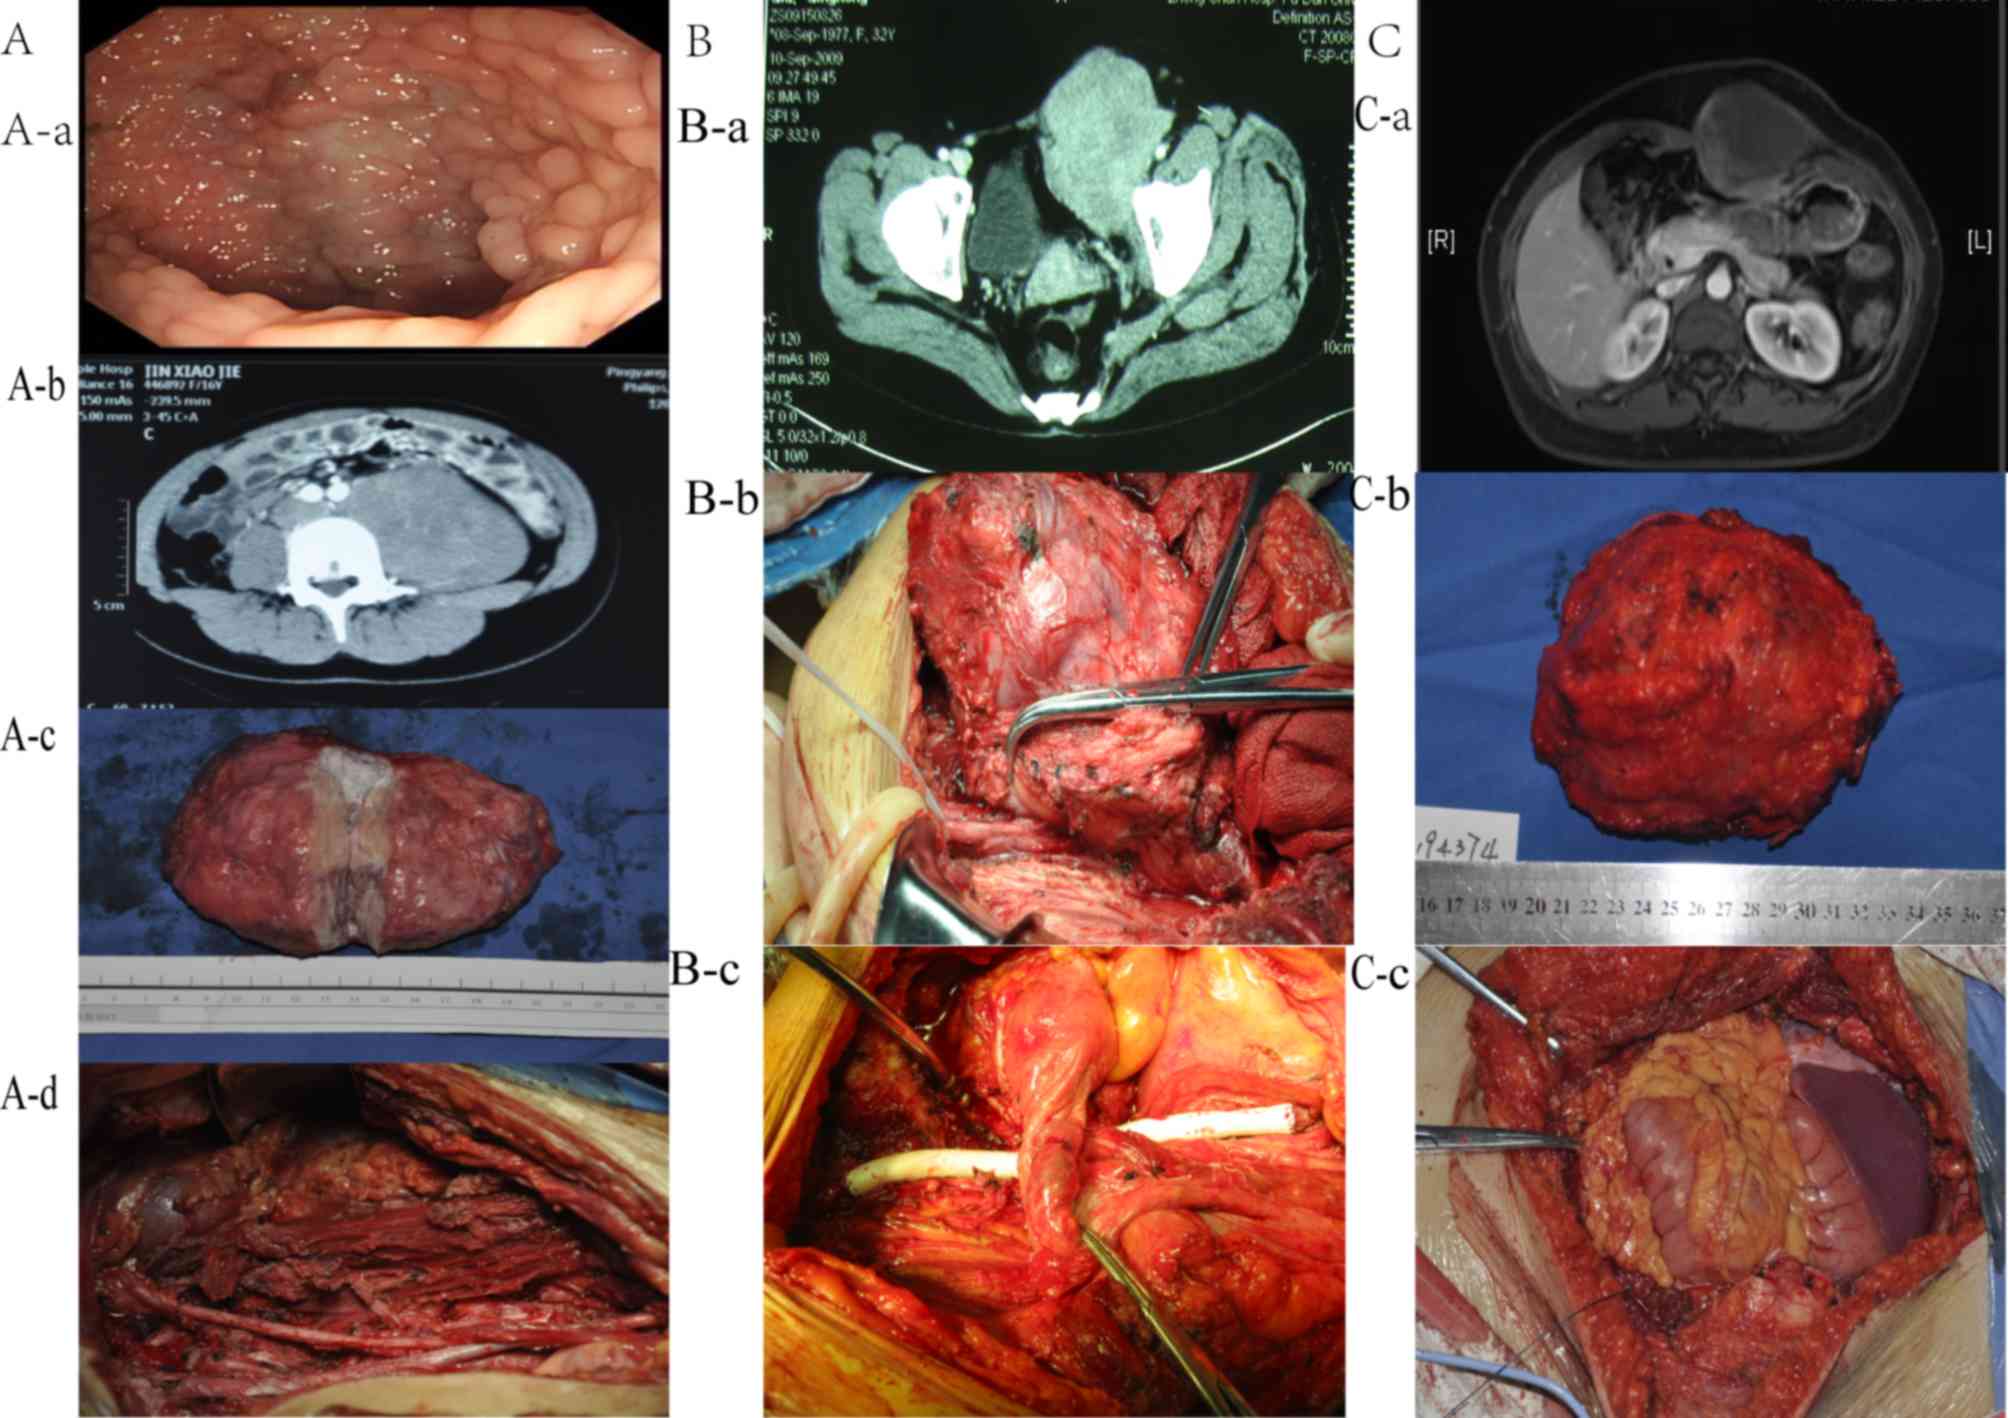

Clinicopathological and molecular characteristics of abdominal desmoid tumors in the Chinese population: A single‑center report of 15 cases

Desmoid tumors (DTs), derived from the abdomen, are a type of rare and aggressive borderline tumor exhibiting high recurrence and malignant potential. The aim of the present study was to investigate the clinicopathological and molecular characteristics of abdominal DT in a Chinese population and to provide clues for selecting the optimal treatment strategy for different types of abdominal DT. The clinicopathological data of 15 consecutive patients with DT was collected. Matched fresh‑frozen tumor tissues and peripheral blood samples were used to detect mutations of adenomatous polyposis coli gene (APC), β‑catenin (CTNNB1) and MutY DNA glycosylase (MUTYH) using Sanger sequencing. Pearson's test was conducted to analyze the differences between sporadic DT and familial adenomatous polyposis (FAP) associated with DT. Time to progress (TTP) and overall survival curves were estimated using the Kaplan‑Meier method and compared using the log‑rank test. A review of the patient clinicopathological characteristics revealed that FAP‑associated DT exhibited a higher rate of abdominal surgery history (P=0.011), with no significant differences in any other characteristics. Sequencing revealed that mutations in the APC, CTNNB1 and MUTYH genes were common in DT, and only one patient harbored no mutations in these genes. Survival analyses revealed that patients with FAP exhibited shorter TTP (P=0.030). Log‑rank test demonstrated a tendency towards shorter TTP in the cases where an R2 resection was performed (P=0.072) and a tendency towards poor prognosis in the cases of DT associated with FAP (P=0.087). In conclusion, Abdominal DTs were prone to occur in patients with FAP with a history of abdominal surgery. Mutations in the APC, CTNNB1 and MUTYH genes were detected in patients with DTs. To the best of our knowledge, this is the first study of abdominal DT occurrence in patients with MUTYH‑associated FAP. The prognosis of DT associated with FAP may be worse compared with that of sporadic DT.

Figure 1